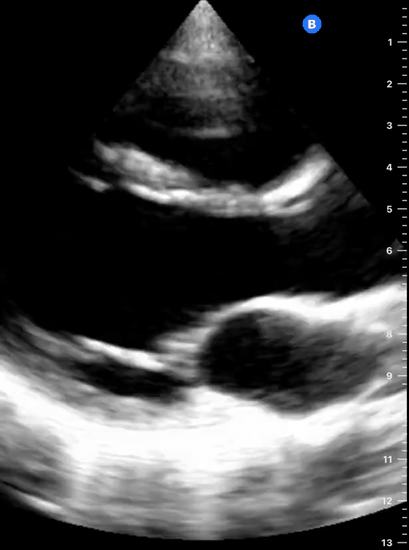

This is the standard window taught in FAST and might be the only one available during cardiopulmonary resuscitation (CPR). This view uses the liver as an acoustic window. To obtain good visualization is essential to handle the probe almost parallel to the anterior abdominal wall, trying to place it under the xiphoid process, pointing to the left shoulder. A deep inspiration or half inspiration can be useful to bring the heart closer to the probe and improve visualisation.

Remember that in the cardiac preset, the screen marking is on the right side. As a result, and unlike the FAST exam, the probe marking points towards the patient’s left. This view is used mainly to look for pericardial fluid, but it also provides information about ventricle size, chamber relationship and valvular abnormalities.